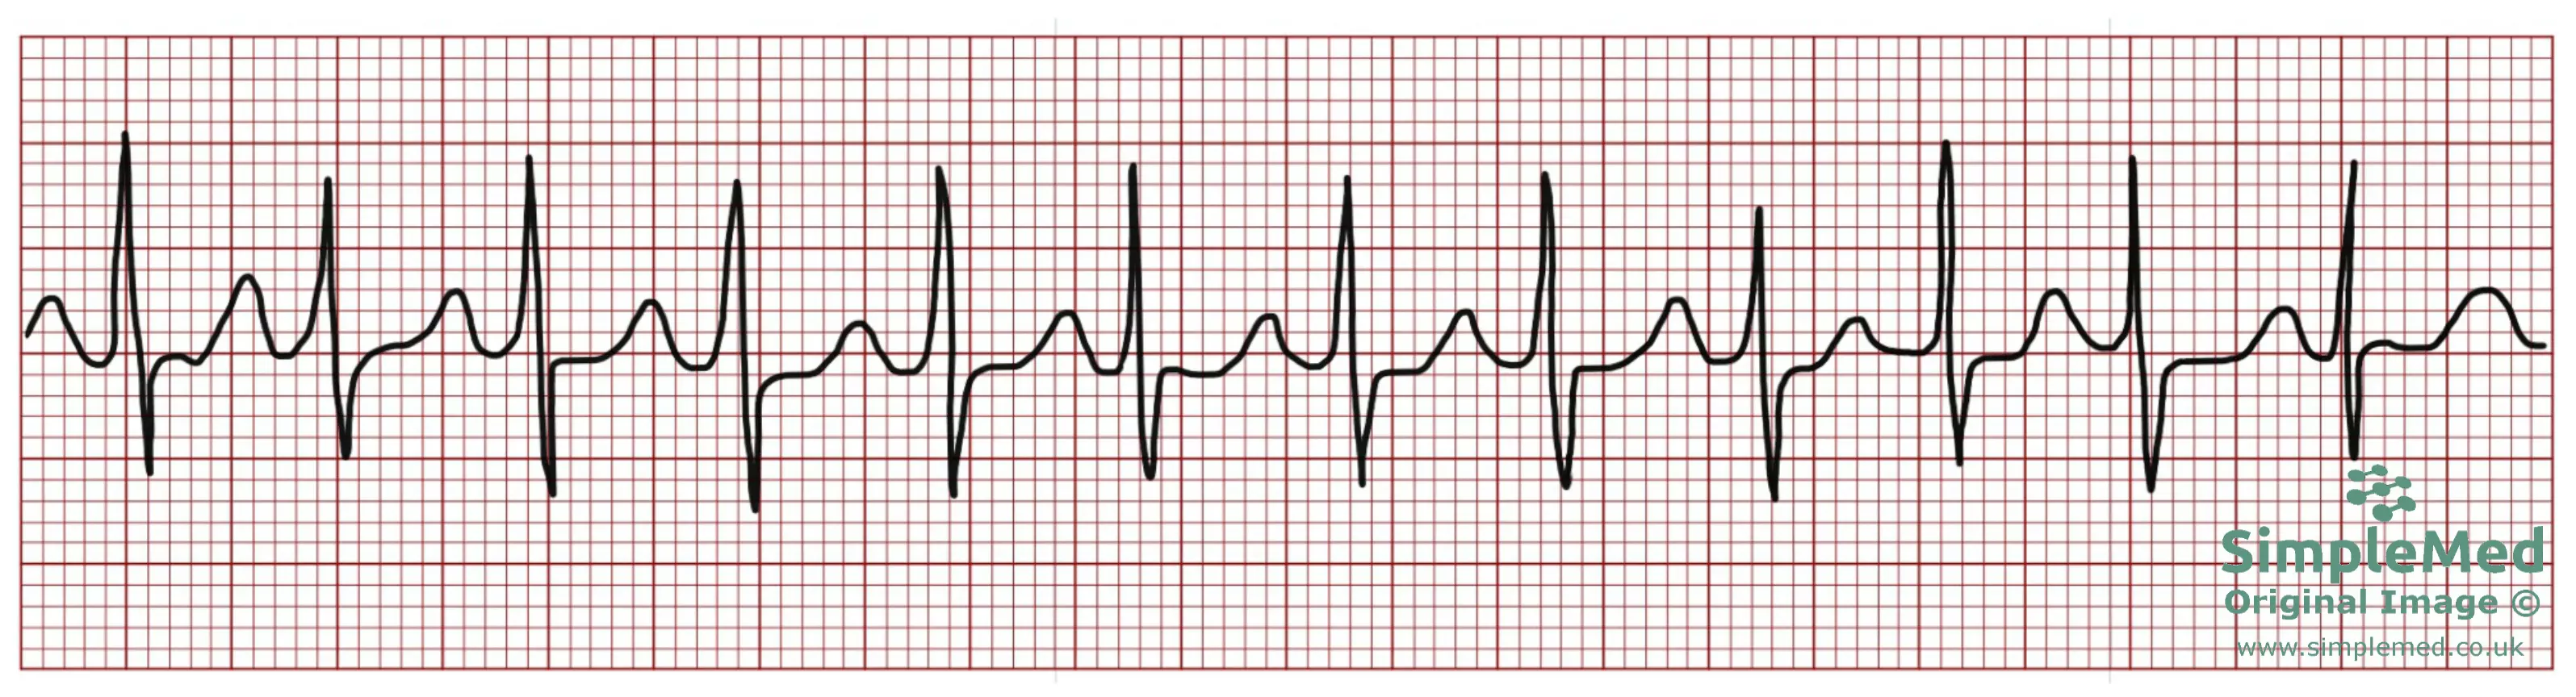

Diagram - Atrial Fibrillation on an ECG. Note the wavy baseline and irregular R-R intervals

SimpleMed original by Dr. Bethany Turner